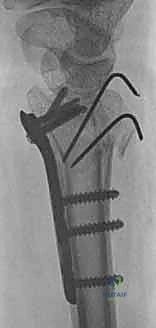

3. كسور الجزء الكردوسي الكردوسي (Ulnar Metaphyseal Fractures)

الجزء الكردوسي هو العنق أو المنطقة الانتقالية التي تربط رأس الزند بجسم العظم (Diaphysis).

هذه المنطقة تحتوي على عظم إسفنجي (Cancellous bone) وهي عرضة للكسور المفتتة (Comminuted fractures) خاصة عند كبار السن المصابين بهشاشة العظام، أو في حالات الحوادث عالية الطاقة. الكسر هنا يؤدي إلى قصر في طول عظم الزند، مما يغير من ميكانيكية توزيع الأحمال في المعصم ويسبب متلازمة انحشار الزند (Ulnar Impaction Syndrome).

ثانياً: العلاج الجراحي (Surgical Intervention)

متى يقرر الدكتور هطيف ضرورة التدخل الجراحي؟

1. عدم الاستقرار (Instability): إذا كان المفصل الزندي الكعبري البعيد (DRUJ) غير مستقر بعد تثبيت كسر الكعبرة.

2. الانزياح (Displacement): إذا كان الكسر في قاعدة الناتئ الإبري منزاحًا بأكثر من 2 ملم.

3. الكسور المفصلية: أي كسر يخل بتطابق السطح المفصلي لرأس الزند.

4. الكسور المفتتة: في الجزء الكردوسي التي تؤدي إلى قصر عظم الزند.

5. الكسور المفتوحة (Open Fractures): حيث يبرز العظم من الجلد، وتتطلب جراحة طارئة لتنظيف الجرح وتثبيت الكسر لمنع العدوى.

خطوات التدخل الجراحي الدقيق مع الأستاذ الدكتور محمد هطيف

تُعد جراحات المعصم والزند من الجراحات الدقيقة التي تتطلب مهارة عالية، وهو المجال الذي يتفوق فيه الأستاذ الدكتور محمد هطيف بفضل استخدامه لتقنيات الجراحة المجهرية (Microsurgery) والأدوات الجراحية ذات التقنية العالية.

1. التخطيط ما قبل الجراحة (Pre-operative Planning)

يقوم الدكتور هطيف بدراسة الأشعة المقطعية ثلاثية الأبعاد بدقة، ويختار نوع وحجم الصفائح المعدنية (Plates) والمسامير (Screws) المناسبة لكل مريض بناءً على حجم العظم ونوع الكسر.